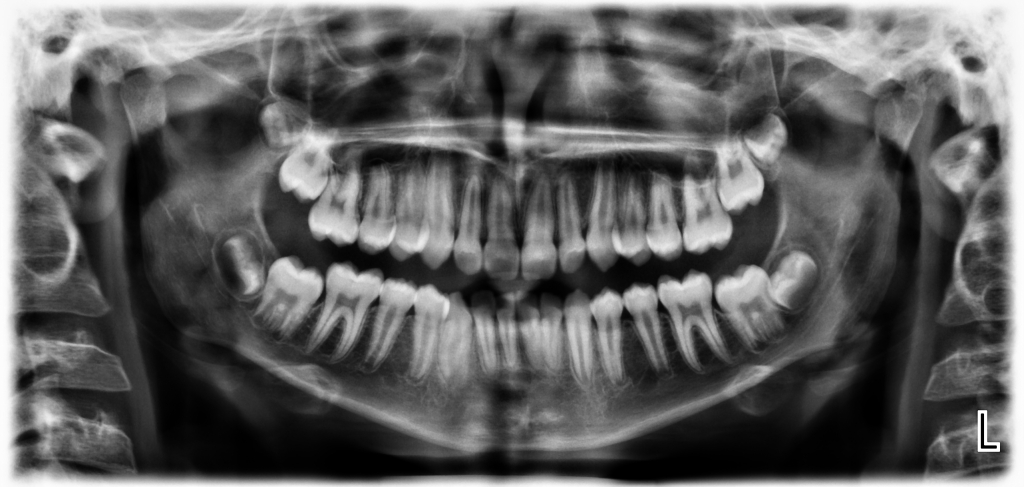

Панорамна рентгенография

Панорамна рентгенова снимка или ортопантомография – ОПГ дава възможност за цялостен обстоен изглед на съзъбието, челюстите, максиларните синуси и темпоромандибуларните стави. Необходима за оценка на общата анатомия на челюстите, околоностните кухини и свързаните с тях патологии.. Панорамната рентгенова снимка е наложен стандарт в ежедневна практика на денталния лекар. Необходима при първоначален преглед за снемане на подробен зъбен статус и изготвяне на добър лечебен план . Чрез панорамната рентгенова снимка могат да бъдат диагностицирани много патолагични процеси, фрактури и травми, кисти и положението им спрямо костта, състоянието на алвеоларния гребен, съотношението между синусния контур и апексите на зъбите, преди и след оперативни интервенции в лицевочелюстната хирургия, при имплантологично лечение, проследяване на апикални и периодонтални изменения, при ортодонско лечение.